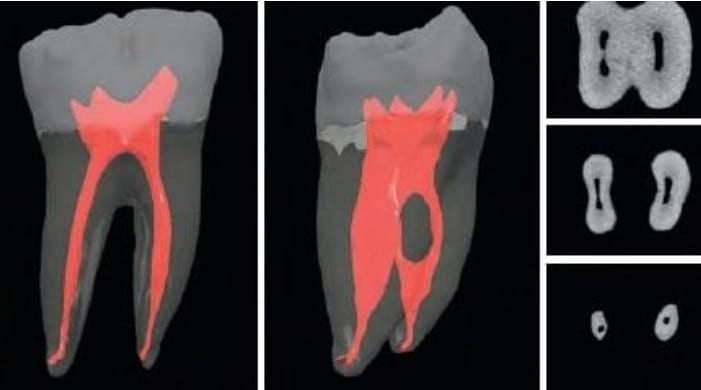

Кт зуба рядом

Кт зуба рядом 109 фотографий